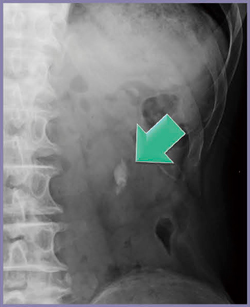

腹部単純撮影(KUB)では,左下腎杯の結石が明瞭に描出されている(図4←)。Dual Energy Scanでは80kVのCT値が高く,尿酸結石とは明らかに異なるパターンを示した(図5)。赤外分光分析の結果,症例2の結石成分はシュウ酸カルシウムであった。Dual Energy Scanでは,尿酸結石とカルシウム結石の物質弁別が可能であることが確認された。

図4 症例2:腹部単純X線画像

明瞭に描出される左腎杯結石(←)